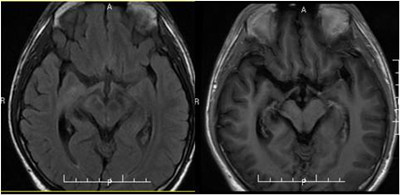

经过治疗,小磊口角右歪的症状减轻,左侧肢体活动较前灵活,左侧肢体乏力好转。复查MR提示肿瘤较前缩小,考虑放疗有效,诊断上支持生殖细胞瘤,继续行全脑全中枢放疗。

2014年10月 放疗结束时